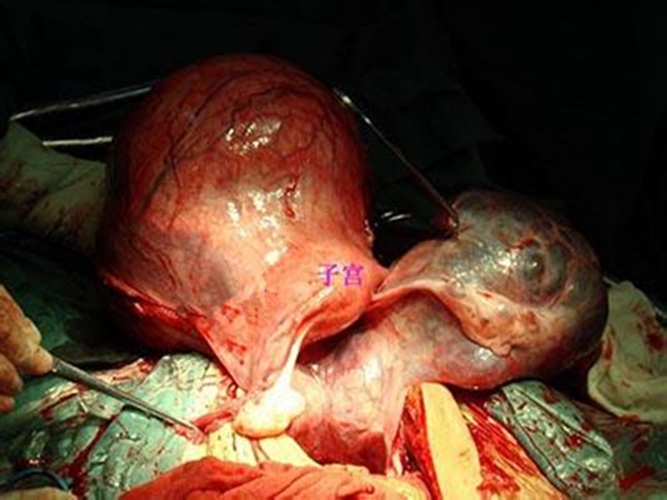

子宮巧克力囊腫

子宮肌瘤巧克力囊

實拍巧克力囊腫